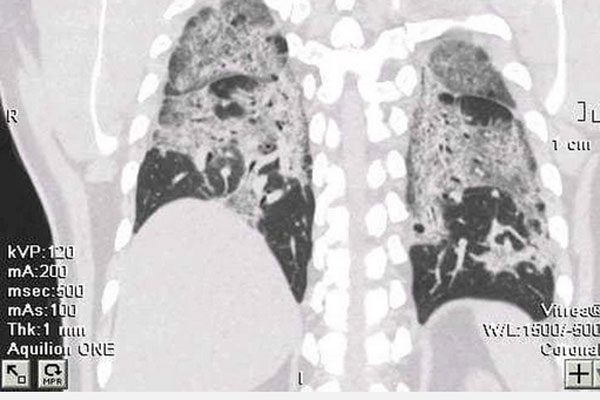

Sau điều trị Covid-19, bệnh nhân lại rơi vào tình trạng hậu Covid-19 thường xuyên thấy khó thở, đi lại cũng mệt, lúc nào cũng thấy “ngộp”. Bệnh nhân tới kiểm tra sức khoẻ, bác sĩ cho chụp phổi để đánh giá tổn thương phổi thì hết sức bất ngờ vì phổi của bệnh nhân trắng xoá do tình trạng xơ phổi diễn tiến.

Bà T. đi khám hậu Covid-19, kết quả chụp X-quang cho thấy xơ phổi hậu Covid, tổn thương xơ phổi nặng hai bên. Tình trạng tổn thương dạng mô kẽ rải rác hai phổi, xơ rải rác hai phổi, giãn phế quản rải rác hai phổi. Bà T. phải điều trị dài ngày, đến nay chưa khỏi.

Hình ảnh phổi của bệnh nhân trắng xoá do xơ phổi tiến triển

Để xác định bạn có bị xơ phổi hay không, TS Vinh cho biết người bệnh cần chụp X-quang phổi. Nhiều trường hợp trên phim X-quang xuất hiện nhiều dải xơ, đám xơ, phổi trắng nhưng cũng có trường hợp xơ phổi ít không nhìn rõ cần chụp thêm CT để phổi được chụp nhiều hình ảnh hơn nhằm xác định tình trạng xơ phổi.